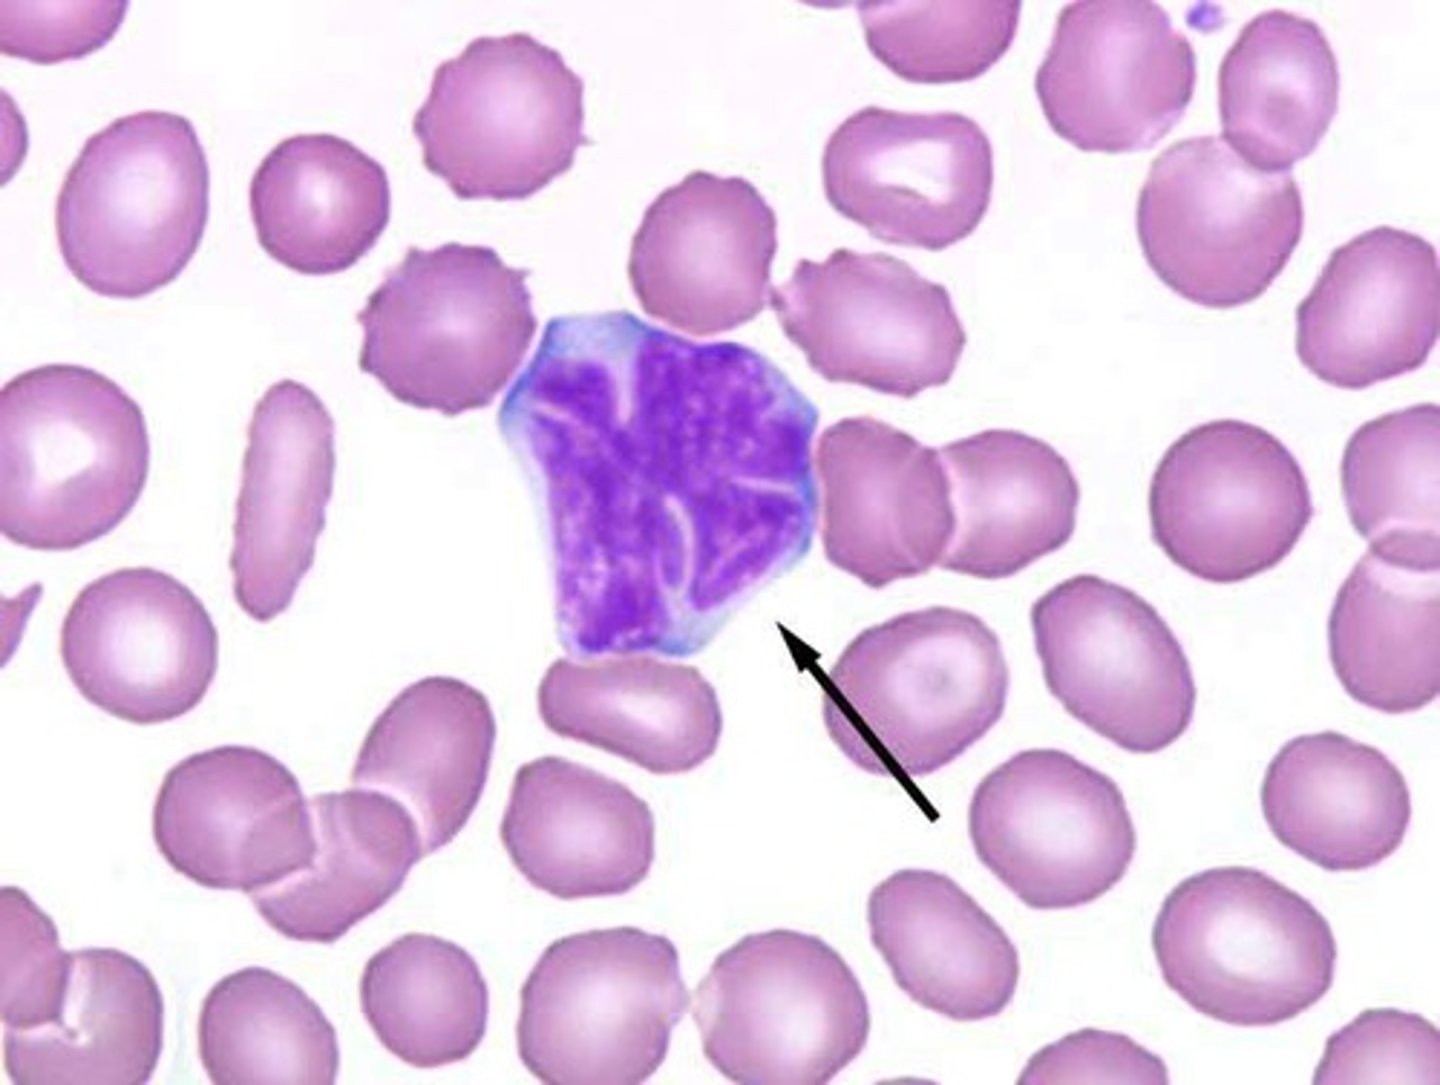

Hepatosplenomgaly, pancytopenia, osteoporosis, aseptic necrosis of femur, bone crises in child

Gaucher disease macrophage (glucocerebrosidase deficiency)

#1 lysosomal storage disease

Build up of glucocerbroside

"Crinkled tissue paper cells"